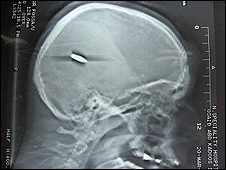

They produced an X-ray image that shows a bullet lodged in the skull of one of the victims.

X-ray  of Osayed Qadus's skull showing a bullet lodged inside